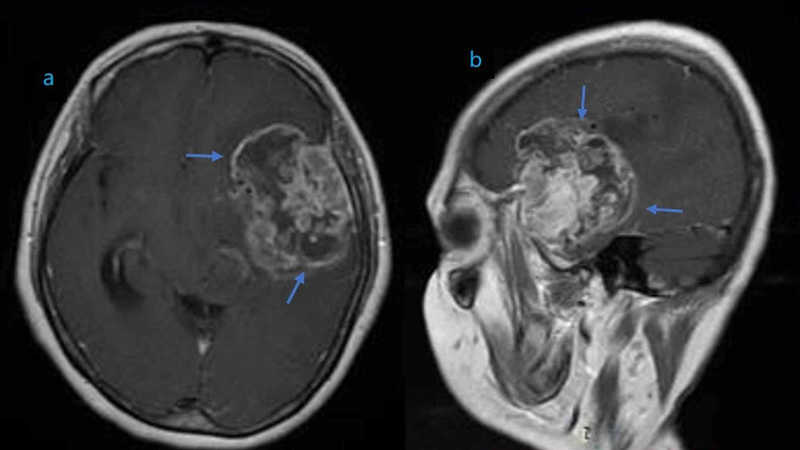

Đặc điểm hình ảnh của các khối u này trên các phương tiện chẩn đoán như MRI (Chụp cộng hưởng từ) và CT (Chụp cắt lớp vi tính) thường hiển thị sự không đồng nhất, với các vùng đậm độ cao và thấp. Sự không đồng nhất này phản ánh sự đa dạng của các tế bào u và môi trường xung quanh chúng. Các đặc điểm này không chỉ quan trọng trong việc chẩn đoán mà còn có ảnh hưởng đến quyết định điều trị.

Chụp cộng hưởng từ (MRI) là công cụ không thể thiếu, cung cấp hình ảnh chi tiết của cấu trúc não và khối u. MRI giúp xác định kích thước, vị trí và đặc điểm cấu trúc của u, hỗ trợ trong việc lập kế hoạch điều trị. Sinh thiết não, mặc dù xâm lấn hơn, cung cấp thông tin về loại tế bào và tính chất của khối u, từ đó hỗ trợ trong việc xác định chẩn đoán và lựa chọn phương pháp điều trị phù hợp.